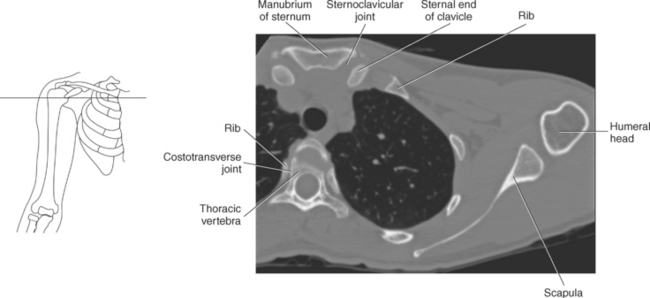

The bony anatomy that comprises the shoulder girdle includes the clavicle, scapula, and humerus (Figures 9.2 and 9.3).

The clavicle connects the upper limb to the trunk of the body and provides attachments for several muscles and ligaments. The clavicle is a long, slender S-shaped bone located anteriorly that extends transversely from the sternum to the acromion of the scapula. The widened sternal end of the clavicle articulates with the clavicular notch of the sternal manubrium to form the sternoclavicular (SC) joint, and its flattened acromial end articulates with the acromial process of the scapula to form the acromioclavicular (AC) joint. The medial two thirds of the body of the clavicle are convex anteriorly, whereas the lateral one third is flattened and concave anteriorly (Figures 9.2 through 9.6).

The scapula is a triangular-shaped flat bone that forms the posterior portion of the shoulder girdle. It has a medial margin, a lateral margin, and a superior margin. The margins are separated by the superior, inferior, and lateral angles (Figures 9.2 and 9.3). The anterior surface of the scapula, subscapular fossa, is flat and slightly concave. The posterior surface of the scapula is divided by the scapular spine into a smaller supraspinous fossa, and a larger infraspinous fossa (Figure 9.7). Four projections of the scapula provide attachment sites for the muscles and ligaments contributing to the shoulder girdle. These include the scapular spine, acromion, coracoid process, and glenoid process (Figures 9.7 through 9.10). The scapular spine arises from the upper third of the posterior surface of the scapula and extends obliquely and laterally to give rise to a flattened process termed the acromion. Located on the anterolateral surface of the scapula is a beaklike process termed the coracoid process, which arises just medial to the glenoid process and functions to protect the shoulder joint, which lies beneath it. The coracoid process is an attachment site for the pectoralis minor, short head of the biceps brachii, and the coracobrachialis muscles. The scapular notch is located just medial to the coracoid process, on the superior margin of the scapula and allows for the passage of the suprascapular nerve (Figure 9.2). The glenoid process, the largest of the projections, forms the lateral angle of the scapula and ends in a depression called the glenoid fossa (glenoid cavity) (Figures 9.7 through 9.9). There are two tubercles associated with the glenoid fossa, an upper supraglenoid tubercle and a lower infraglenoid tubercle, which serve as attachment sites for the biceps brachii and triceps brachii (Figure 9.8). The shallow articular surface of the glenoid fossa joins with the relatively large articular surface of the humeral head to create the freely moving glenohumeral joint (Figures 9.2, 9.3, 9.11, and 9.12).